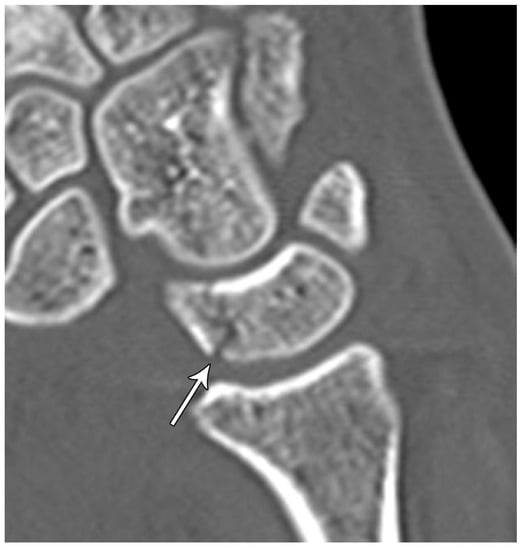

The wrist includes the distal ends of the radius and ulna, eight carpal bones, and proximal bases of the metacarpal bones [4]. The carpal bones are divided into a proximal row and distal row. The proximal row, consisting of the scaphoid, lunate, triquetrum, and pisiform bones, is considered an intercalated segment between the radius and distal carpal row. The proximal row is central to maintaining wrist stability by balancing movement and regulating the forces sent to and from the hand and the forearm. The distal row consists of the hamate, capitate, trapezoid, and trapezium bones, which form a more stable and rigid alignment than the proximal row as they function to support the bases of the metacarpals [5]. The arcs of the Gilula are used on PA wrist radiographs as part of assessing the normal alignment of the carpus (Figure 1). There are three arcs:

• Proximal (first) arc—smooth line along the proximal surfaces of the scaphoid, lunate, and triquetrum.

• Middle (second) arc—smooth line along the distal surface of the scaphoid, lunate, and triquetrum.

• Distal (third) arc—smooth line along the proximal surface of the capitate and hamate, closely paralleling the second arc.

Figure 1. PA radiograph of the wrist depicting the arcs of Gilula. The 1st arc (red) outlines the proximal surfaces and the 2nd arc (yellow) the distal surfaces of the scaphoid, lunate and triquetrum. The 3rd arc (white) outlines the proximal surfaces of the capitate and hamate.

Life 13 01426 g001

In a biomechanically normal wrist, there should be no irregularities in the contour of these arcs when traced. Any step-offs/disruptions in these lines suggest a ligamentous injury or fracture at the site of the broken arc [6]. Exceptions include two normal variants, one where the triquetrum is shorter than the lunate creating a step-off of the first arc but normal second arc, and a second when a type II lunate can cause a bilobed appearance of the second and third arcs between the capitate and hamate [7].